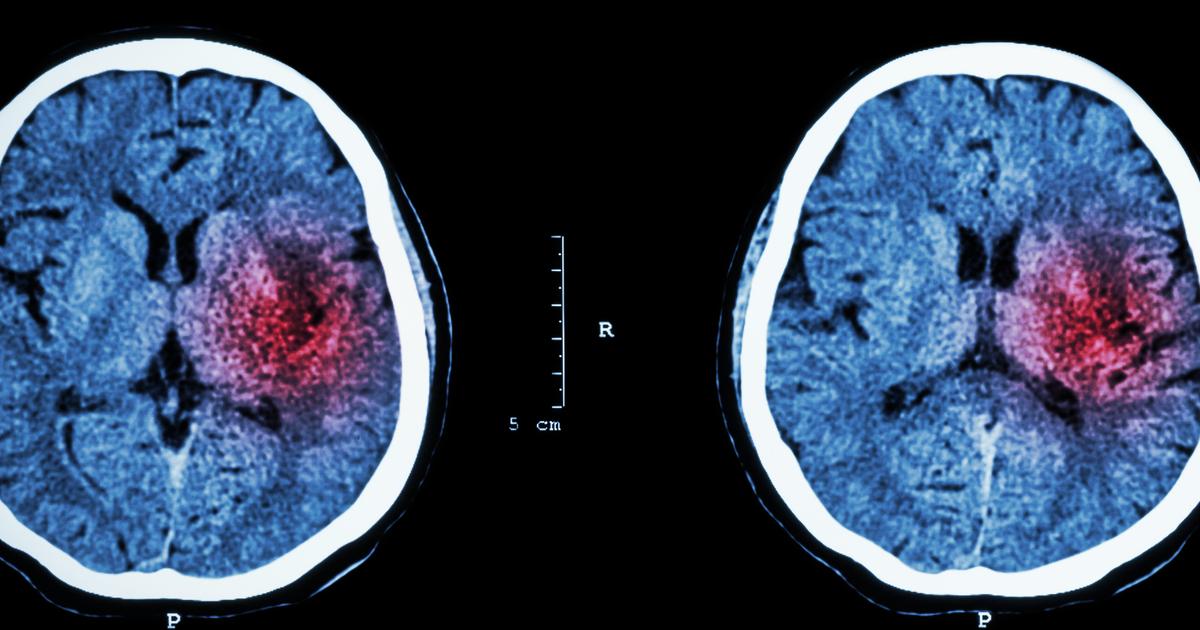

Hemorrhagic Stroke

Hemorrhagic stroke is a type of stroke caused by the leakage of blood from an artery located in the brain. Blood gets into the surrounding brain tissue when an individual has a blood vessel that has become weakened and bursts. Brain cells become damaged from the pressure placed on them by the leaked blood, causing the damaged tissue to be unable to function correctly. Hemorrhagic stroke has two different subtypes: subarachnoid hemorrhage and intracerebral hemorrhage. An intracerebral hemorrhage that causes a stroke occurs when the bleeding is isolated to the inside of the brain tissue. A subarachnoid hemorrhage that precipitates a stroke occurs when the blood is leaked into the space between the patient's brain and the protective membranes that cover it. To treat these types of strokes, the bleeding in the brain must be mediated, and the pressure in or on the brain tissues must be reduced to prevent further permanent brain damage.